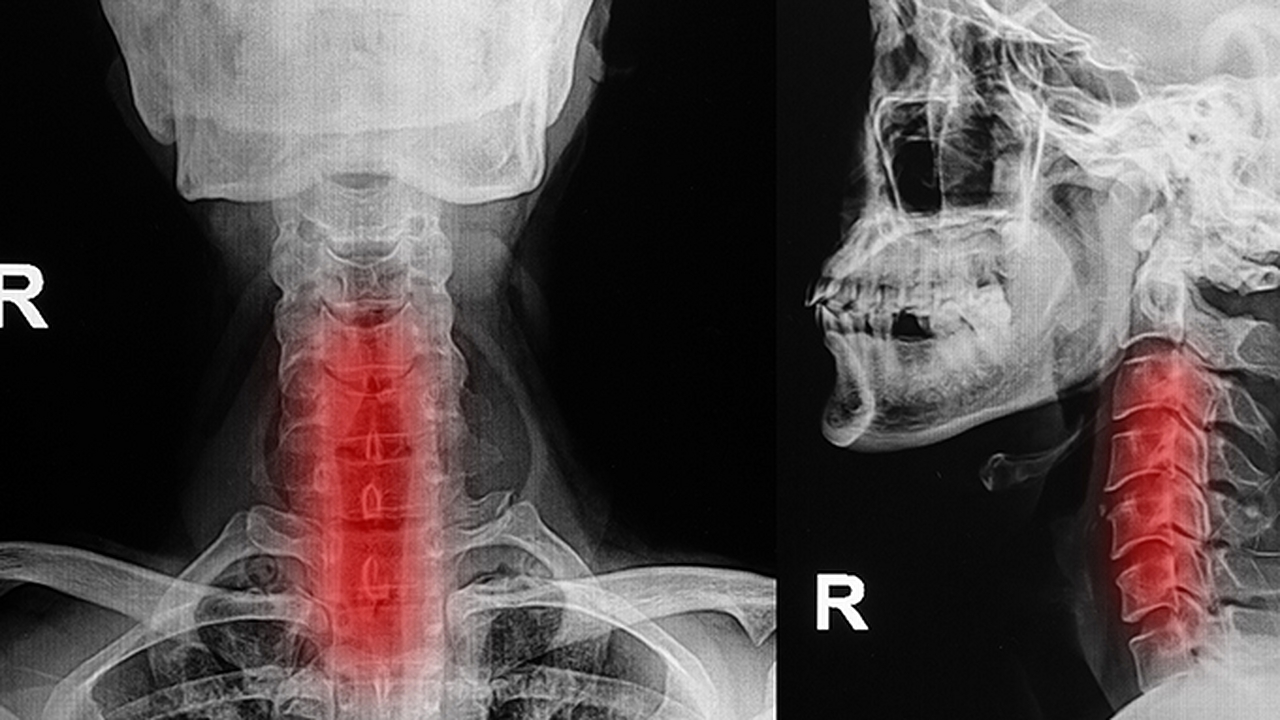

3、上呼吸道感染

病毒或細菌感染可引起急性咽炎,咽喉充血腫脹導(dǎo)致干燥感和通氣障礙。多伴有發(fā)熱、咳嗽等癥狀。需進行血常規(guī)檢查,可遵醫(yī)囑使用阿莫西林克拉維酸鉀片、藍芩口服液等藥物控制感染。